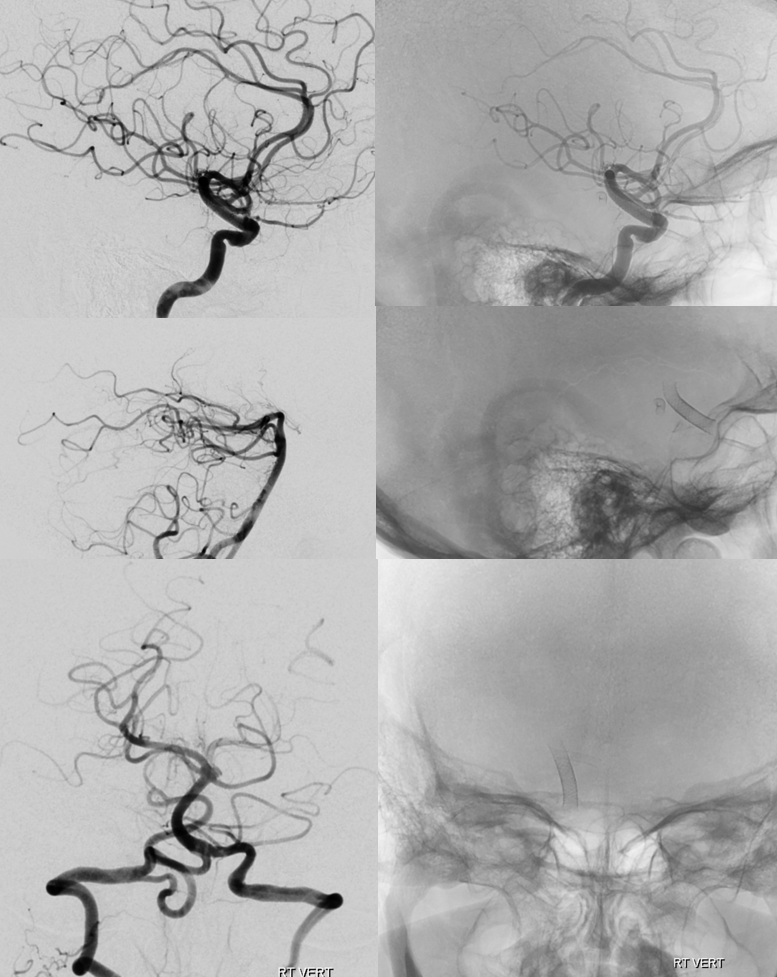

This is a not so aggressive looking PCOM. Not small but also not very ominous-appearing

Post 2 PEDs. Typically, with a good P1, this is plenty. Note strategic high coverage over the aneurysm and single choroidal coverage

Two years later — two more pipes are added. Can one argue this is a mistake — if two did not do it, will four? Its a valid point, as you can guess

One year after, still here… What we dont understand is why. What we do know is that one Pipe would have surely not been enough. It is also possible that having all these Pipes stopped the aneurysm from growing much more… Never know, but we have sure seen what happens when these are underterated

What to do? Coiling it through P1 risks the thalamoperforator. Undercoiling is not a good idea. The solution is to Pipe across the P1

This is changing flow dynamics for sure. One year later, finally gone. Note how the aneurysm deflated, closing the distance between the two pipe constructs.